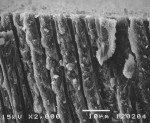

The SEM images in Figure 3 show close-up views of cross-sections of untreated (Figure 3a) and Q-treated (Figure 3b) dentin. The coherent nature of the 2-µ to 3-µ thick surface layer on this part of the treated dentin was clearly seen, and bonding of deposited mineral with the dentin surface was apparent.

Figure 4a, Figure 4b and Figure 4c provides SEMs of cross sections of the dentin, which was treated with each of the calcium- and phosphate-containing fluoride toothpastes—E, AHECS, and AHEC. Each figure shows mineral covering the dentin surface and blocking most of the tubules. The layer produced by AHECS looked very similar to that resulting from treatment of dentin with the professional desensitizer. Furthermore, it appeared to be strongly bonded to the dentin.

This study’s finding of calcium phosphate deposition by the professional desensitizer was similar to that found by Tung et al who determined sequential applications of calcium and phosphate solutions to dentin disks produced a layer of ACP and resulted in significant reductions of as much as 99.9% in dentin permeability.12,16 However, examination of the SEMs indicated the deposit formed in the authors’ study was more crystalline than that formed on the dentin in studies by Tung et al. As previously mentioned, ACP is unstable in the presence of moisture and known to transform into other less soluble crystalline calcium phosphate salts. Fluoride reportedly catalyzes the transformation of ACP to apatitic mineral.10 Depending on how soon after treatment the SEM was obtained, ACP, HAP, or mixtures of the two could be present. In this study, it appeared the mineral had largely transformed into the more crystalline HAP mineral. The SEM of the dentin cross section shows a highly coherent nature and a strong bond with the dentin surface.

The calcium- and phosphate-delivering toothpastes apparently operate by a similar mechanism to the professional desensitizer, producing ACP that transforms into HAP on the surface of the dentin, sealing tubules and reducing dentin permeability. The morphology of the surface mineral produced by E and AHEC is not clearly seen in these SEMs. However, the mineral created by AHECS appeared strikingly similar to that made by Q. In both cases, the mineral appeared strongly bonded to the dentin surface.